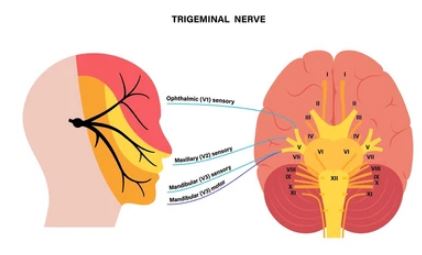

J Dent (Shiraz). 2024 Mar; 25(1): 17–25. Published online 2024 Mar 1. doi: 10.30476/dentjods.2023.95758.1889 PMCID: PMC10963861 PMID: 38544777 Efficacy of Laser Therapy in Trigeminal Neuralgia: a Systematic Review Sara Haghighat, DMD Student,1 Fahimeh Rezazadeh, DMD, MScD,2 Hossein Sedarat, MD Student,3 Amir

Study of the outcome of patients undergoing pulsed radiofrequency for the treatment of Trigeminal Neuralgia: An observational study. Neha Sharma, Iqra Nazir Naqash, Zulfiqar Ali, Nadeem Ahmad Khan, Ravouf P Asimi, Imtiyaz A